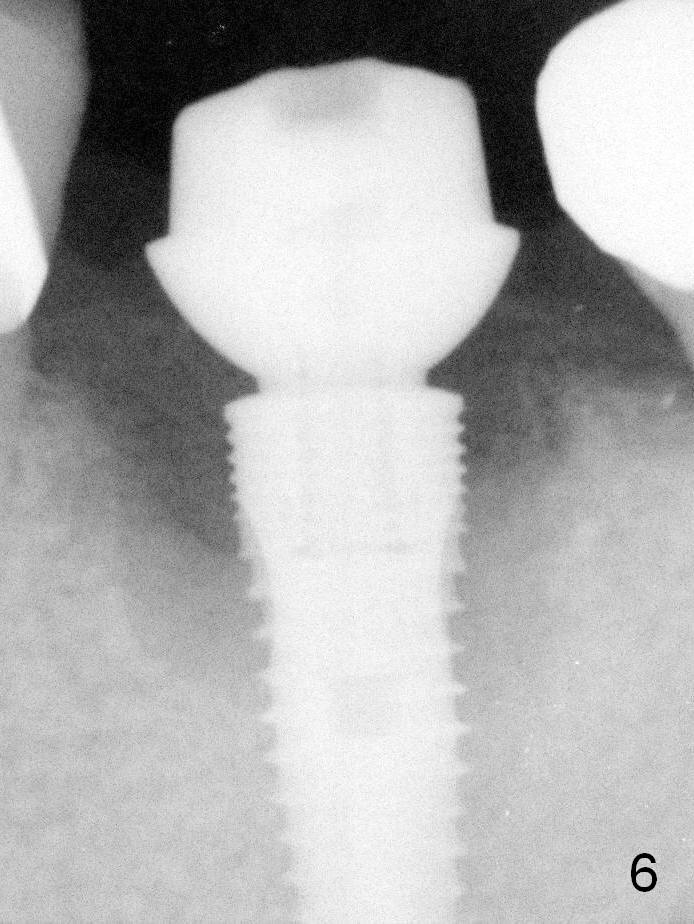

As expected, the lingual margin of the abutment is suprgingival 2 months postop. The immediate provisional is fractured (Fig.6).